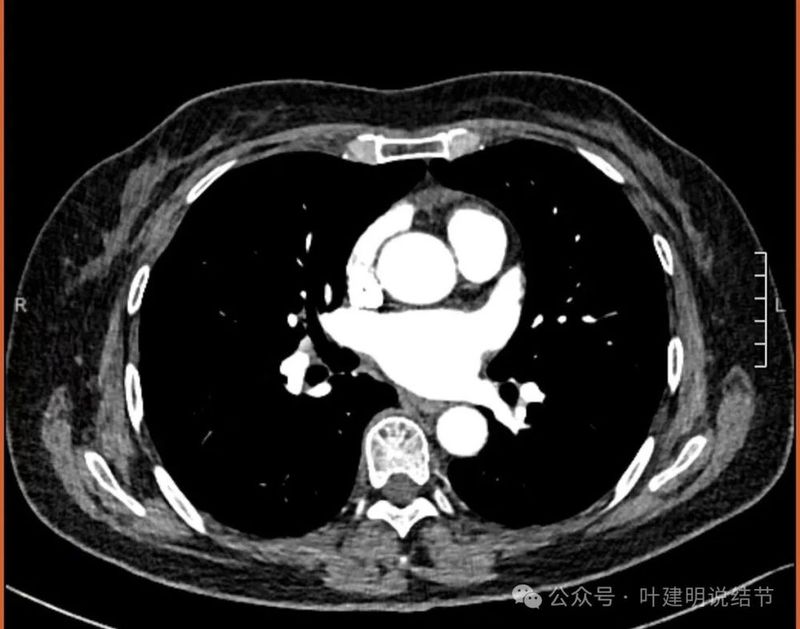

纵隔窗见有明显实性成分,磨玻璃成分不可见,走行血管也明显。

纵隔与肺门没有见到显著增大融合要考虑转移的淋巴结。